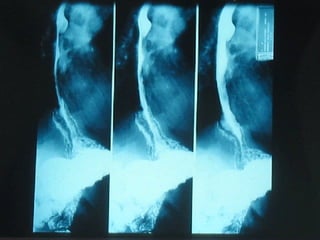

S.E.G.D.  Serie esófago gastro duodenal Definición  Estudio de doble contraste (bario) y aire del tracto digestivo superior. (esófago, estómago, duodeno)

SEGD PATOLOGÍA  ESOFÁGICA A.- Estrechamientos y dilataciones secundarias Acalasia Estenosis Esclerodermia Enf. de Chagas Neoplasia Lesiones por quemadura (cáusticos y dietéticos etc.)

SEGD PATOLOGÌA ESOFÀGICA D.- INFLAMACIÓN: Esofagitis péptica por reflujo Esofagitis por radiación Esofagitis medicamentosa Esofagitis cáustica